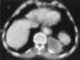

Cavitating pneumonia

Pneumonia is an inflammatory condition of the lung primarily affecting the small air sacs known as alveoli. Symptoms typically include some combination of productive or dry cough, chest pain, fever and difficulty breathing. [Source: Wikipedia ]